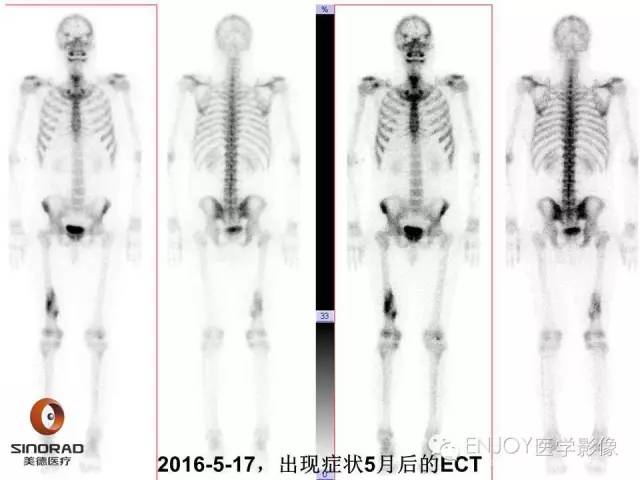

【病例】右侧股骨多形性肉瘤1例X线及MR影像表现

多形性肉瘤(以往称为:恶性纤维组织细胞瘤)